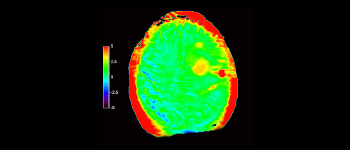

Numa sociedade para a qual os distúrbios neurológicos representam um fardo pesado, a Philips está empenhada em proporcionar uma extraordinária clareza de diagnóstico e orientações de tratamentos para todos os pacientes. Atualmente, embora a RM seja o padrão de excelência no diagnóstico por imagem em neuro-oncologia, sua precisão na classificação de tumores e na avaliação de acompanhamento dos tratamentos pode ser aprimorada. O APT (Amide Proton Transfer) 3D é um método exclusivo de diagnóstico por imagem por RM do cérebro sem contraste que aborda a necessidade de um diagnóstico mais confiante em neuro-oncologia. O APT 3D utiliza a presença de proteínas celulares endógenas para produzir um sinal de RM que se correlaciona diretamente com a proliferação celular, um marcador de atividade tumoral. O APT 3D pode auxiliar profissionais de saúde capacitados na diferenciação entre gliomas de baixo e de alto grau e a diferenciar a progressão tumoral do efeito do tratamento.1